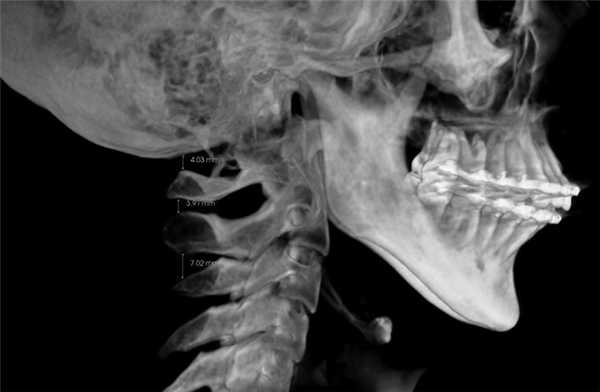

3. Оценка положения шейных позвонков (краниовертебральные функциональные пространства по M. Rocabado). В норме расстояние между C0—CI (затылочная кость и I шейный позвонок) и CI—CII (остистыми отростками I и II шейных позвонков) — 6,5±1—2,5 мм (рис. 8) [14].

4. Краниовертебральное центральное соотношение по M. Rocabado. На КЛКТ также есть возможность анализа ротаций первого и второго шейных позвонков. Измерение проводят от заднего бугорка первого шейного позвонка к зубу второго шейного позвонка, при этом большее расстояние свидетельствует о ротации CI в данную сторону (рис. 9).

Рис. 9. Ротация первого шейного позвонка (CI) вправо, так как расстояние между CI и зубом CII больше с правой стороны — 5,09 мм; слева — 3,43 мм.

Ротации шейных позвонков, уменьшение функциональных пространств служат причиной головных болей напряжения и лицевых болей, поэтому при обнаружении данных патологий необходим комплексный подход в лечении.

При анализе КЛКТ также можно обнаружить увеличенный шиловидный отросток вследствие оссификации шилоподъязычной связки (в норме его длина составляет 2,5—3 см, осложнение — боли при глотании, иррадиирующие в миндалины, боли в области лица, ограничение подвижности шеи, головокружение, пресинкопальные состояния, обмороки) и наличие аномалии Kimmerle (оссификация косой атланто-затылочной связки, проходящей над бороздой позвоночной артерии I шейного позвонка, осложнение — компрессия позвоночной артерии и нарушение мозгового кровообращения), что, возможно, свидетельствует о краниомандибулярных нарушениях у обследуемого. Таким образом, стоматолог может констатировать наличие шилоподъязычного синдрома и других тяжелых осложнений, ухудшающих качество жизни человека (рис.10) [15, 16].

Рис. 10. Удлиненный шиловидный отросток (а) и аномалия Kimmerle (б).